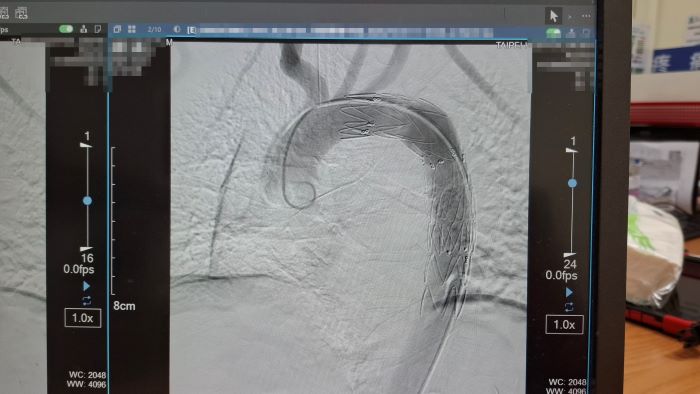

院方緊急會診心臟血管外科醫師孟繁傑,評估後立即施行「胸主動脈腔內血管支架置放手術」,僅在腹股溝處開出不到1公分的小傷口,將支架透過導管送入主動脈破裂處封堵出血點,成功解除致命危機。廖先生術後恢復順利,目前已平安出院。

他說明,「廖先生受傷的位置位於主動脈弓與降主動脈交界處的峽部(isthmus)。」,這裡是胸部外傷最常見的主動脈破裂位置,因為主動脈在此處轉彎固定,當胸部受到強烈撞擊時,產生的剪力容易造成血管撕裂,形成假性動脈瘤。如果沒有及時發現,一旦包覆性破裂轉為完全破裂並引發大出血,存活機率幾乎為零。

孟繁傑表示,近年來,主動脈腔內血管支架置放手術逐漸成為主流治療方式。醫師只需從腹股溝股動脈置入導管,將金屬支架精準送到破裂位置撐開血管並封住破口,不僅傷口小、手術時間短,也能降低出血與併發症風險。目前此項治療方式已被美國血管外科學會列為主要治療建議,台灣健保也已納入給付,讓患者能以較低負擔接受先進治療。